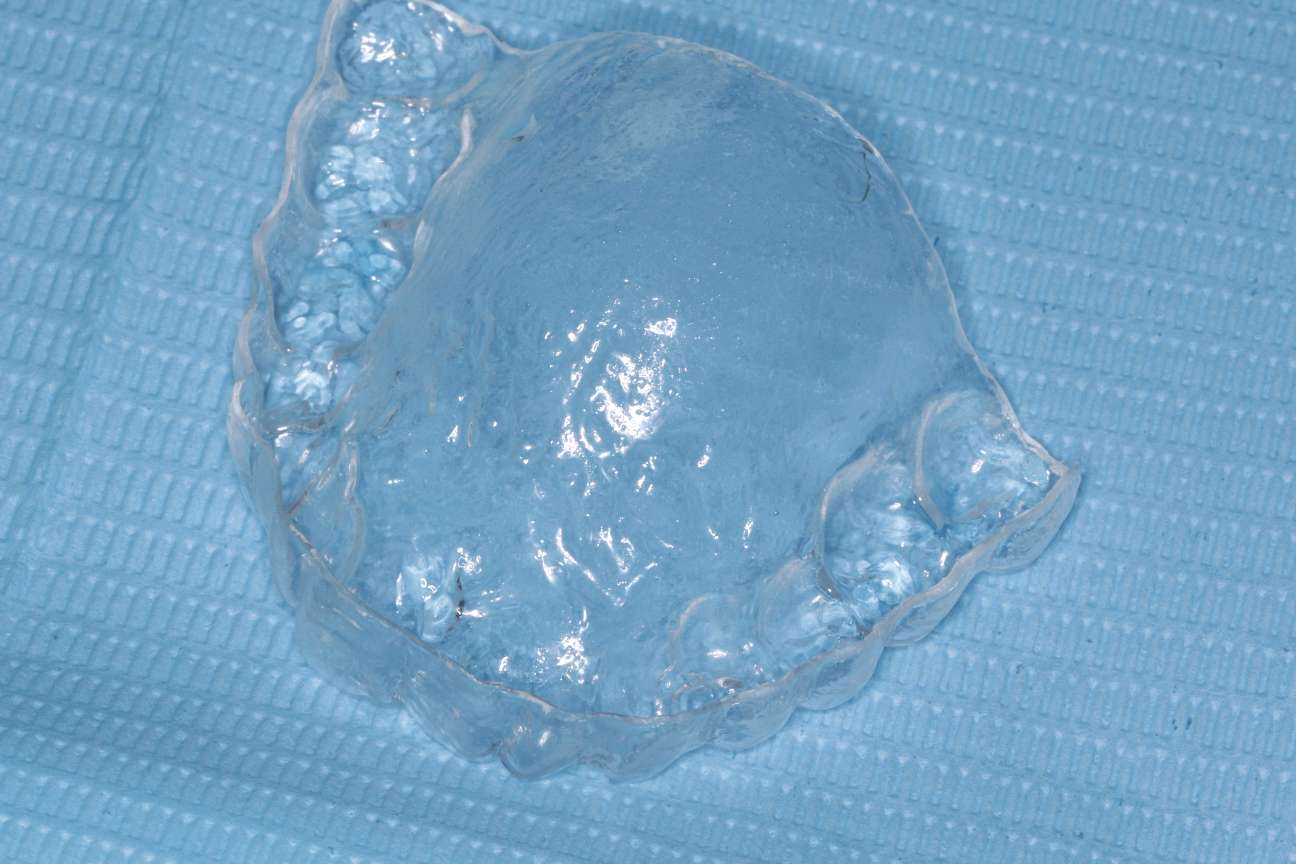

患者女30岁,左下后牙缺失已植入种植体,牙槽嵴呈刀刃壮,附着龈明显不足。角化牙龈缺乏易造成种植体抗炎屏障变弱,容易导致软组织炎症和边缘骨水平吸收。建议患者做游离牙龈移植术。通过获取自体健康游离龈瓣,移植到角化不足的患区,使种植体周围角化组织宽度增加,前庭沟加深。成功的话,会有良好的预后效果。